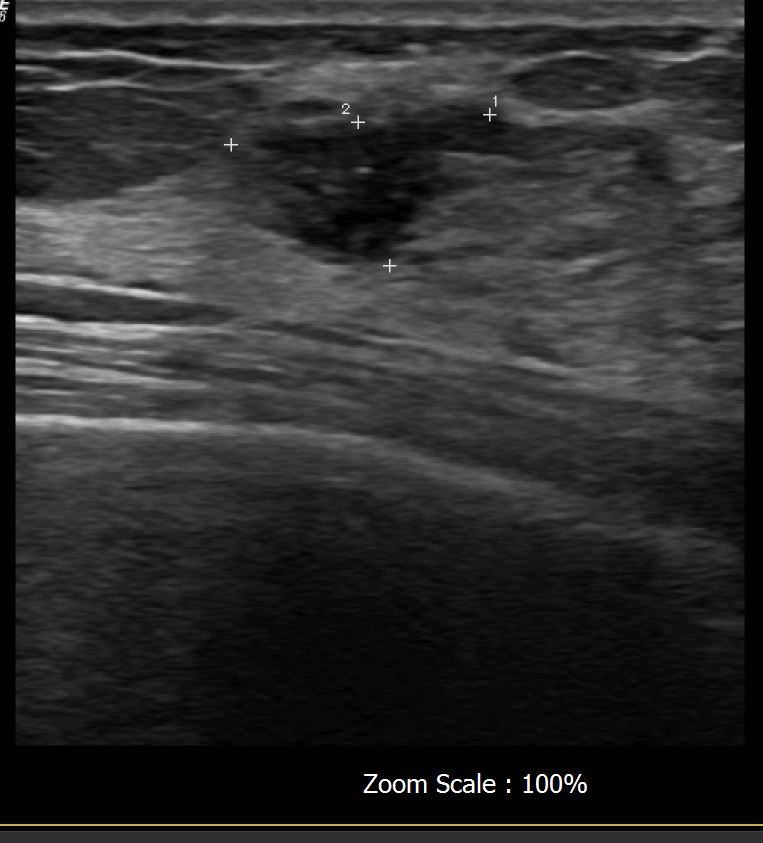

상기 환자 외부검사상 이상소견으로 내원하신 40대 여성으로 우측에 의심스러운혹있어 조직검사 시행후 유방암 진단되었습니다.